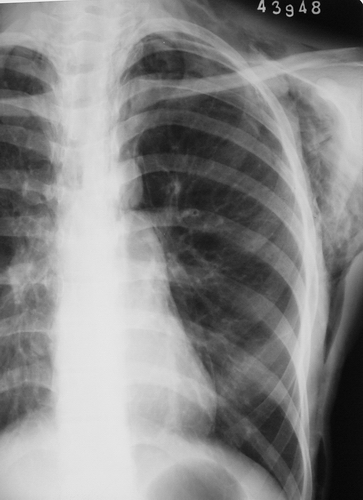

患者,女,18岁。气喘气促多年,加剧半天。摄片如下:

左侧胸壁、腋窝、颈部及右侧颈部皮下软组织内示斑片状、条状低密度气体影,四天后复查片明显吸收好转。